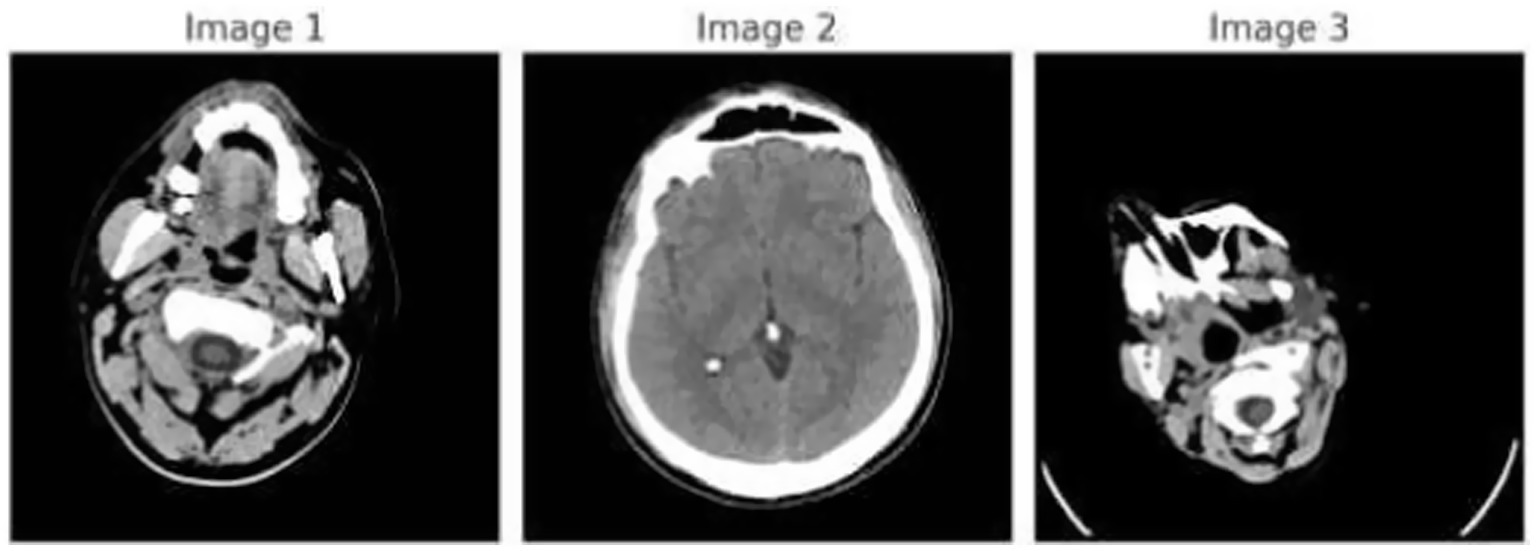

Figure 1 demonstrates the unprocessed and processed CT scan brain scans. Raw images are initially scanned, whereas the processed ones have undergone a procedure of removing noise and normalization to facilitate analysis. Figure 2 shows grayscale, equalized, and edge-detected images of the preprocessed brain images. Gray levels eliminate color, equalization increases contrast, and edge detection emphasizes boundaries of key structures. The CT scan cross-sections shown in Figure 3 are used to obtain details about brain structure and the parts prone to abnormalities such as strokes and tumors. Figure 4 shows different CT scan cross-sections with varying types of stroke, and how ischemic and hemorrhagic strokes can be represented in the brain in a cross-section.

CT scan cross-sections showing brain structure and potential abnormalities.

Figure 4

CT scan cross-sections of brain showing stroke variants.